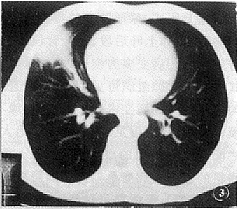

2.5 病变边缘:球形肺炎边缘模糊者12例(57%),余9例边缘清晰但不光滑(43%),其中5例见粗长毛刺(图3)。位于肺野外围的楔形病变其两侧缘较平直。周围型肺癌除2例边缘部分模糊外,余均边缘清晰但不光滑,20例见程度不等的分叶(95%),9例见多发细小毛刺(43%)。

图3 右肺中叶球形肺炎,病变为楔形,边缘见粗长毛刺,病变与肺门间有粗大血管相连